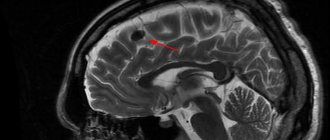

Уточнить локализацию, давность поражения, объем и другие параметры патологического процесса помогают современные методы магнитно-резонансной томографии.